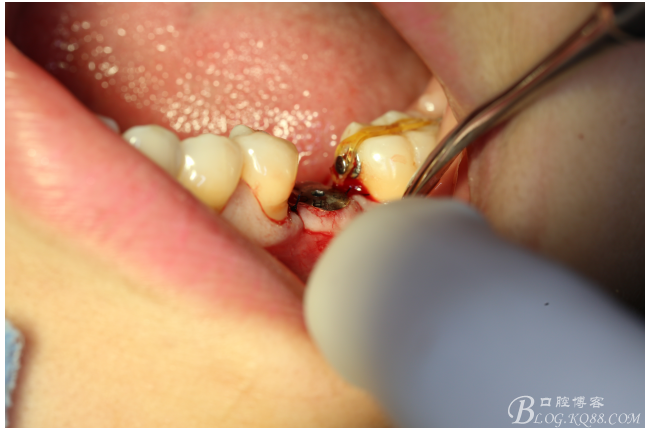

檢查:36.46缺失,36缺牙區(qū)近遠中間隙約3mm,46缺牙區(qū)間隙約0.5mm,37.47.48近中傾斜,48近中面齲壞達牙本質(zhì)淺層,37牙周探診4mm,47近中探診深度5-6mm,不松,口內(nèi)照片及CT片如下:

口內(nèi)照片

處理:必蘭麻局部麻醉切開37遠中牙齦,植入mini支抗釘一枚,37近中鄰面粘舌側(cè)扣,皮鏈輕力牽引,3周更換。